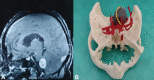

Three-dimensional (3D) printing technology in neurosurgery has gained popularity nowadays. Skull base contains many major neurovascular structures in a confined space, along with anatomical variations making surgical approaches to this region challenging. 3D-printed model of skull base tumors consists of the patient's bony skull base, actual tumor dimensions, and surrounding major neurovascular structures. We included a total number of five patients with skull base tumors (one case of planum sphenoidale meningioma, two cases of sellar tumor with suprasellar extension, and two cases of cerebellopontine angle tumor) and 3D-printed tumor model of each of them. These models were used for preoperative simulation and served as very true to life training tool. These help in increasing the efficacy of the surgeon, improves surgical safety and ergonomics. They were also used for patient counselling, educating about the disease, the surgical procedure, and associated risks.